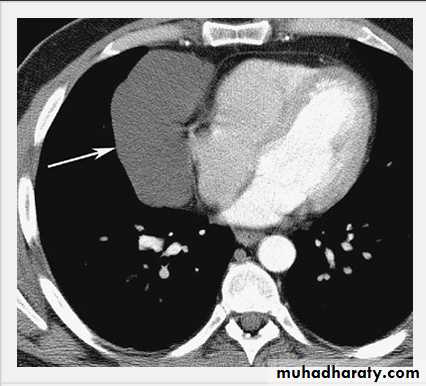

Empyema.

A computed tomography scan shows a posterior left pleural fluid collection (arrow) containing air (dark) and surrounded by thickened pleura.

The thickened pleura appears to be split by the lenticular fluid collection.